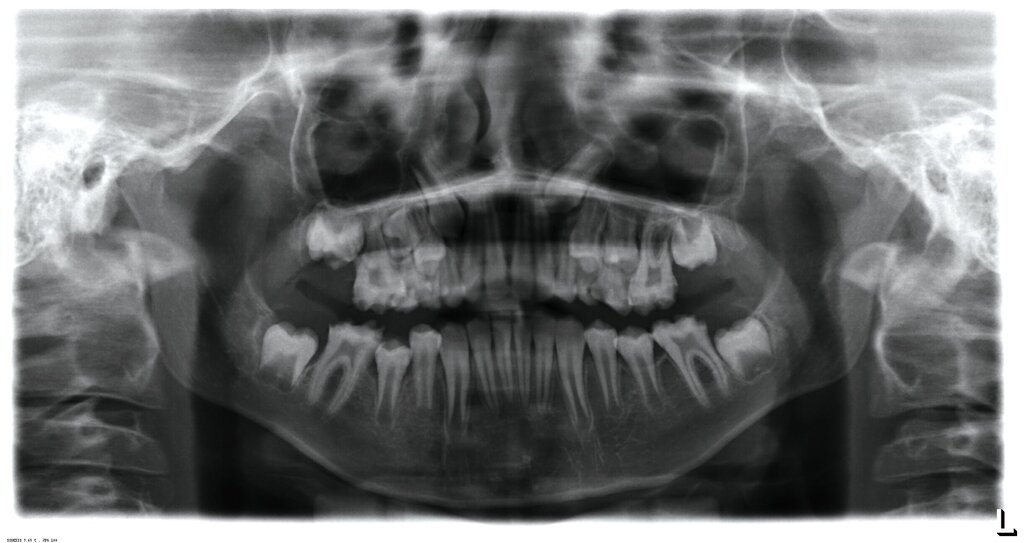

Klinisch zeigten sich ein nicht-kariöses Wechselgebiss mit generalisierter Schmelzhypoplasie an allen Zähnen sowie eine insuffiziente Mundhygiene. Zusätzlich bestanden eine fehlende Mittellinienübereinstimmung, ein Overbite von minus vier Millimetern und ein Overjet von sechs Millimetern (Abbildung 5), die sich phonetisch in einem interdentalen Sigmatismus äußerten. Röntgenologisch waren alle Zähne angelegt, jedoch war der Zahnschmelz stark reduziert oder vollständig fehlend (Abbildung 6).